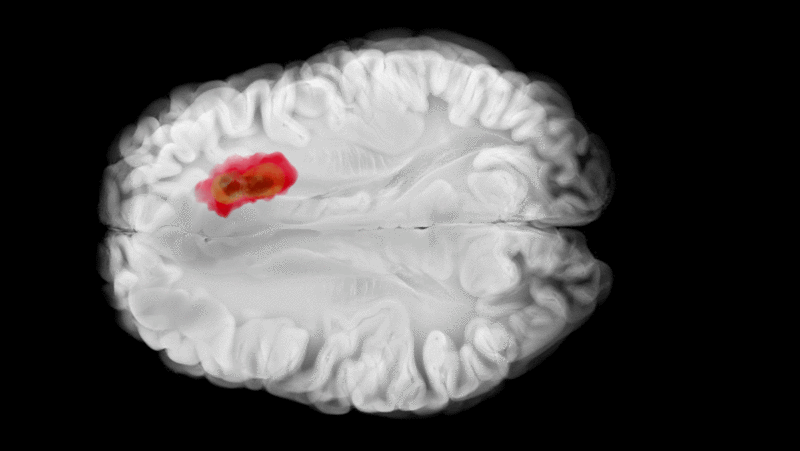

Die Methode ermöglicht es, Zellveränderungen in Echtzeit zu beobachten und zu verstehen, wie Immunzellen im Verlauf von Krankheiten reagieren oder – wie im Fall von Glioblastomen – durch das Tumorumfeld funktionsunfähig gemacht werden.

Mit der neuen Methode konnten Kirschenbaum und Kollegen an Mäusen erstmals die zeitliche Abfolge der Immunreaktion im Glioblastom rekonstruieren. Innerhalb von nur 24 Stunden nach dem Eindringen in das Tumorgewebe verlieren ursprünglich schlagkräftige natürliche Killerzellen (NK-Zellen) ihre Fähigkeit, Krebszellen abzutöten – gesteuert durch das hemmenden Signalmolekül TGF-β. Gleichzeitig verwandeln sich eingewanderte Immunzellen in sogenannte Tumor-assoziierte Makrophagen (TAM), die das Wachstum des Tumors aktiv unterstützen.

Durch die experimentelle Blockade eines wichtigen Immunrezeptors konnten die Forscher diesen Prozess aber umkehren: Statt zu unterdrückenden TAM entwickelten sich die Immunzellen daraufhin zu entzündungsfördernden, tumorkontrollierenden Makrophagen. Das Ergebnis liefert einen wichtigen neuen Ansatz für weitere Untersuchungen, um die Entwicklung zielgerichteter Immuntherapien gegen bislang therapieresistente Tumorarten wie das Glioblastom voranzutreiben. Dafür hat die Jury Daniel Kirschenbaum den Langener Wissenschaftspreis 2025 zuerkannt.